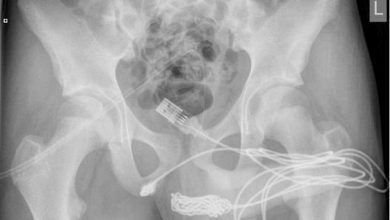

15-year-old Suffers Horrible Penis Accident as USB Cable Gets Stuck in His Blokus